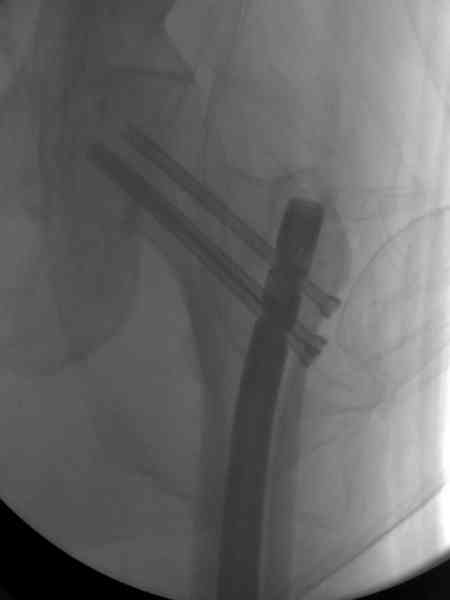

В первый же день произведено антеградное штифтованием DePuy Trochanteric Nail.

На второй день (7) обнаружен пропущенный перелом,

и проведены шурурпы через и спереди штифта без удаления.

Послеоперационные снимки